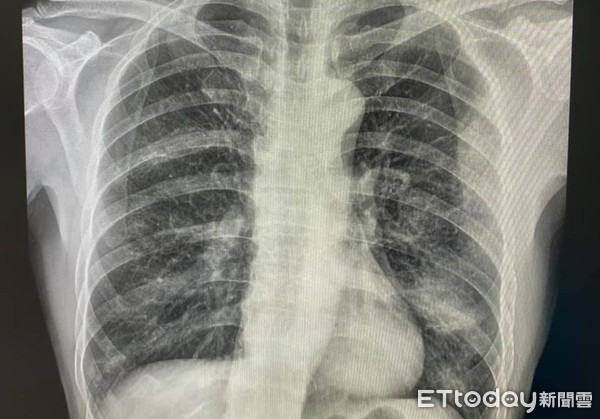

柯世祐說,打開門一看,病患被抽血,小女孩張大著嘴巴,嚎啕大哭,彷彿在向病毒

控訴;X光傳來看起來左下的肺炎,又是一個需要住院的病人,「我跟男人告知需要住